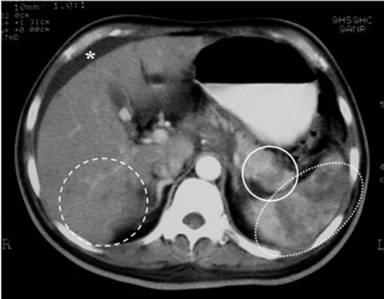

The most commonly affected part of the pancreas was the body region (100%; Figure 1), followed by the head (75%; Figure 2) and tail (50%; Figure 3). The involvement was typically multi-focal (75%; Figures 1 and 2) and in the form of micro-abscesses. Only one patient (25%) had a large focal solitary abscess (Figure 1), affecting the body of the pancreas. Other associated pancreatic findings included splenic vein thrombosis (Figure 2), peripancreatic inflammations and peri-pancreatic fat streaking. Extra-pancreatic manifestations included blood (4 patients), liver abscesses (3 patients; multiple micro-abscesses (Figures 3 and 4) or large ‘honeycomb’-like abscesses), ascites (2 patients; Figures 3 and 4), splenic abscesses (2 patients; Figures 2 and 4) (which also has the ‘honeycomb’ appearance), psoas abscesses (2 patients) and lung (1 patient).

Figure 4. Axial computed tomography image showing hypoechoic lesions in the tail of the pancreas consistent with pancreatic abscesses (circle), splenic abscess (dotted oval), micro-abscesses in the liver (dashed circle) and ascites (asterisk) (Case #4). |